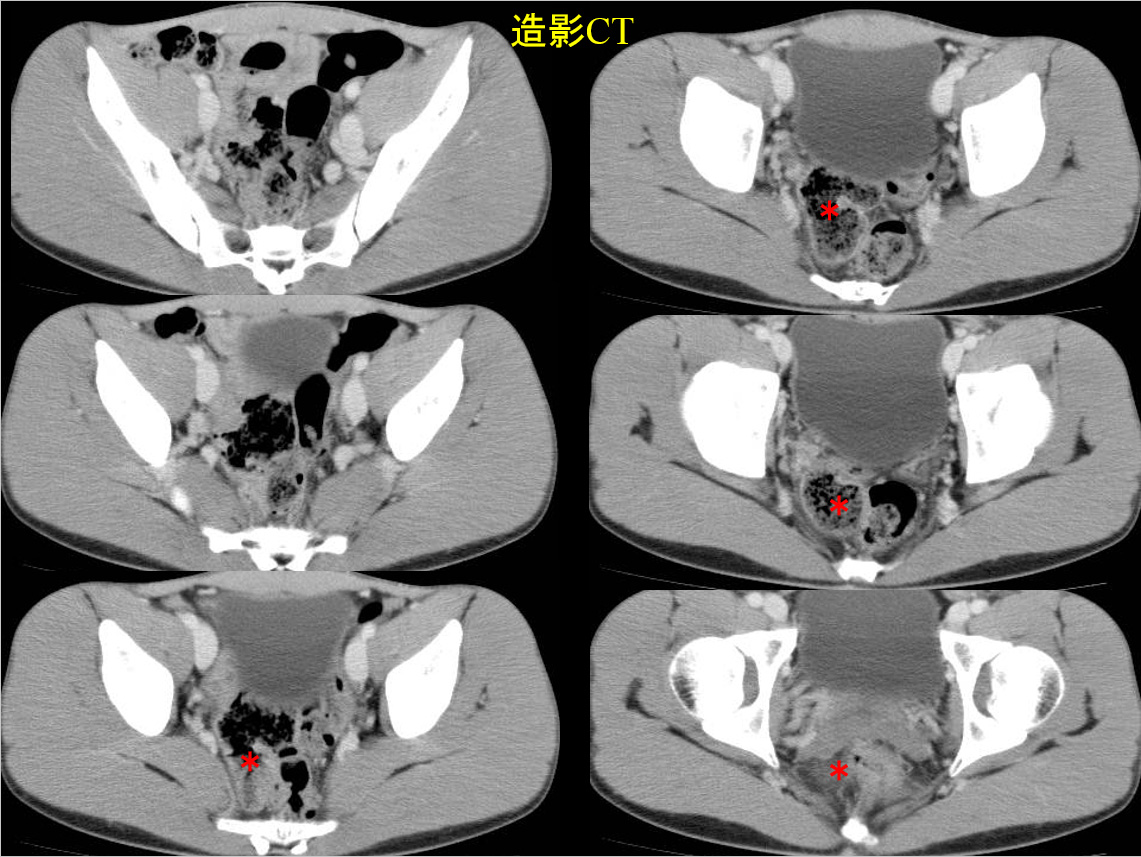

• 造影CT(腹部〜骨盤部):水平断像のみ

• 造影CT

CT水平断のみでは、一見して異常所見の指摘は困難(便塊の貯留した直腸との鑑別が困難)である。

MRでは、骨盤内に大きな嚢胞性病変を認める。

骨盤内の嚢胞性病変の鑑別となるが、男性であるため卵巣由来は否定的である。水平断像および冠状断像を丹念に読影すると、同病変は小腸と連続しており、腸管構造の一部であることがわかる。病変の局在は回腸末端に近く、年齢、経過を加味すると、メッケル憩室が最も考えられる。